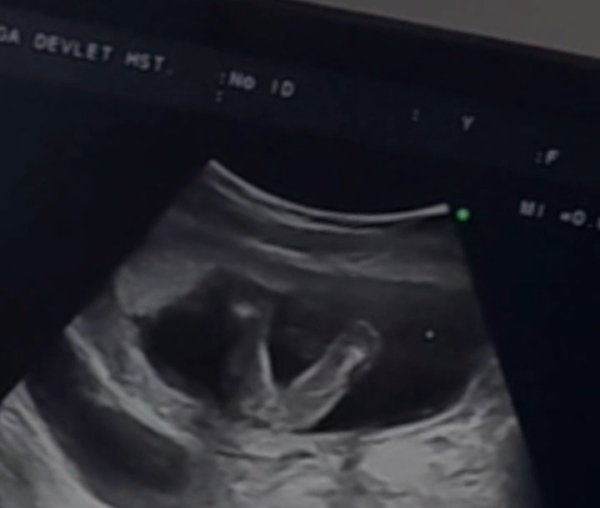

Elimde sadece bu görüntüler var dünden. Videodan alıntı yaptım ama kıza benziyor gibi doktor da emin olamıyor o yüzden ayrıntılıya kalacak.

• Screenshot_20230616-205701_Video Player.jpg

Screenshot_20230616-205701_Video Player.jpg

20,7 KB · Görüntüleme: 129

Selamlar hayatım net olmamakla birlikte göndermiş olduğun ilk resimden kız olarak görüyorum Allah her şeyin hayırlısını bilendir hayırlısı nasip olsun